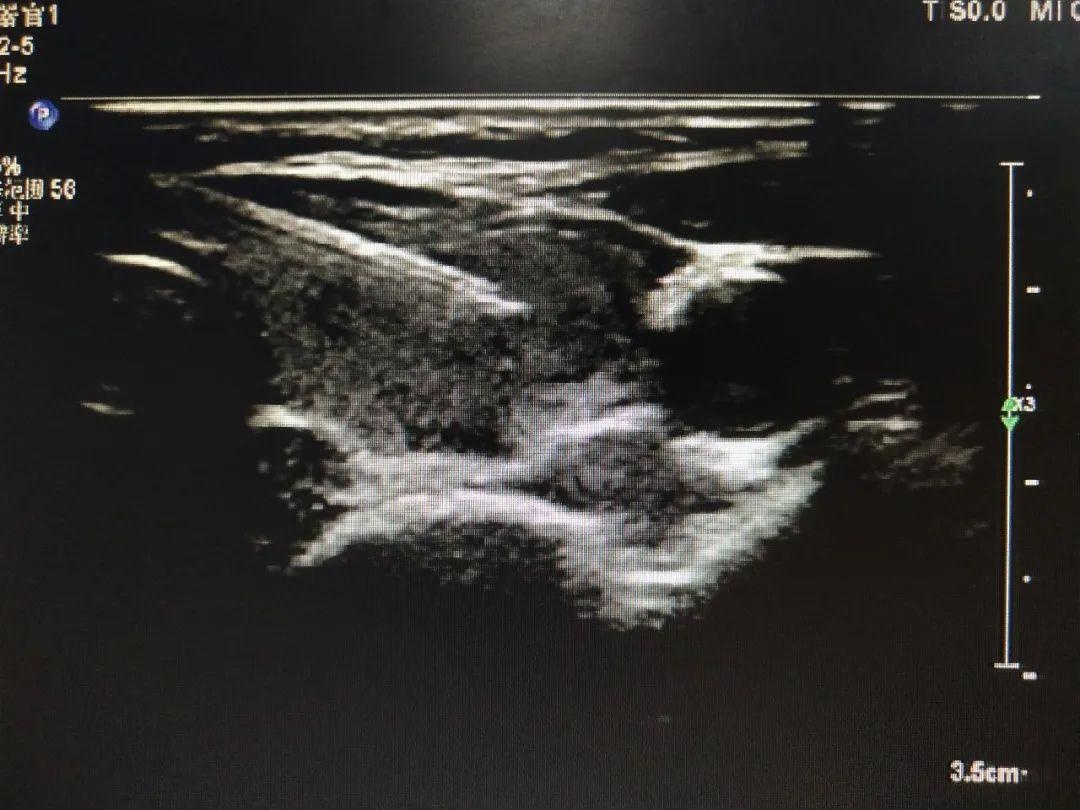

图1 超声介入穿刺手术示意图

为防止病情进一步加重,需尽早的胆道引流减压,胆道引流减压首先需要减黄。超声科陈锋主任会诊后为刘女士进行了超声引导下经皮经肝胆管穿刺置管引流术(PTCD)。在陈锋主任的指导下江芳强主治医师、李北冰主管护师在超声引导局部麻醉下行经皮经肝胆管穿刺引流术,术后引流通畅,减压减黄明显,刘女士腹痛缓解,全身情况好转,6天后行外科手术,术后一周康复出院。

图5经皮经肝胆管穿刺置管引流术